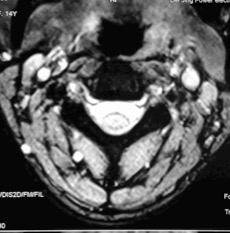

何女士术前核磁检查显示:多节段颈椎间盘退变导致神经根炎症产生